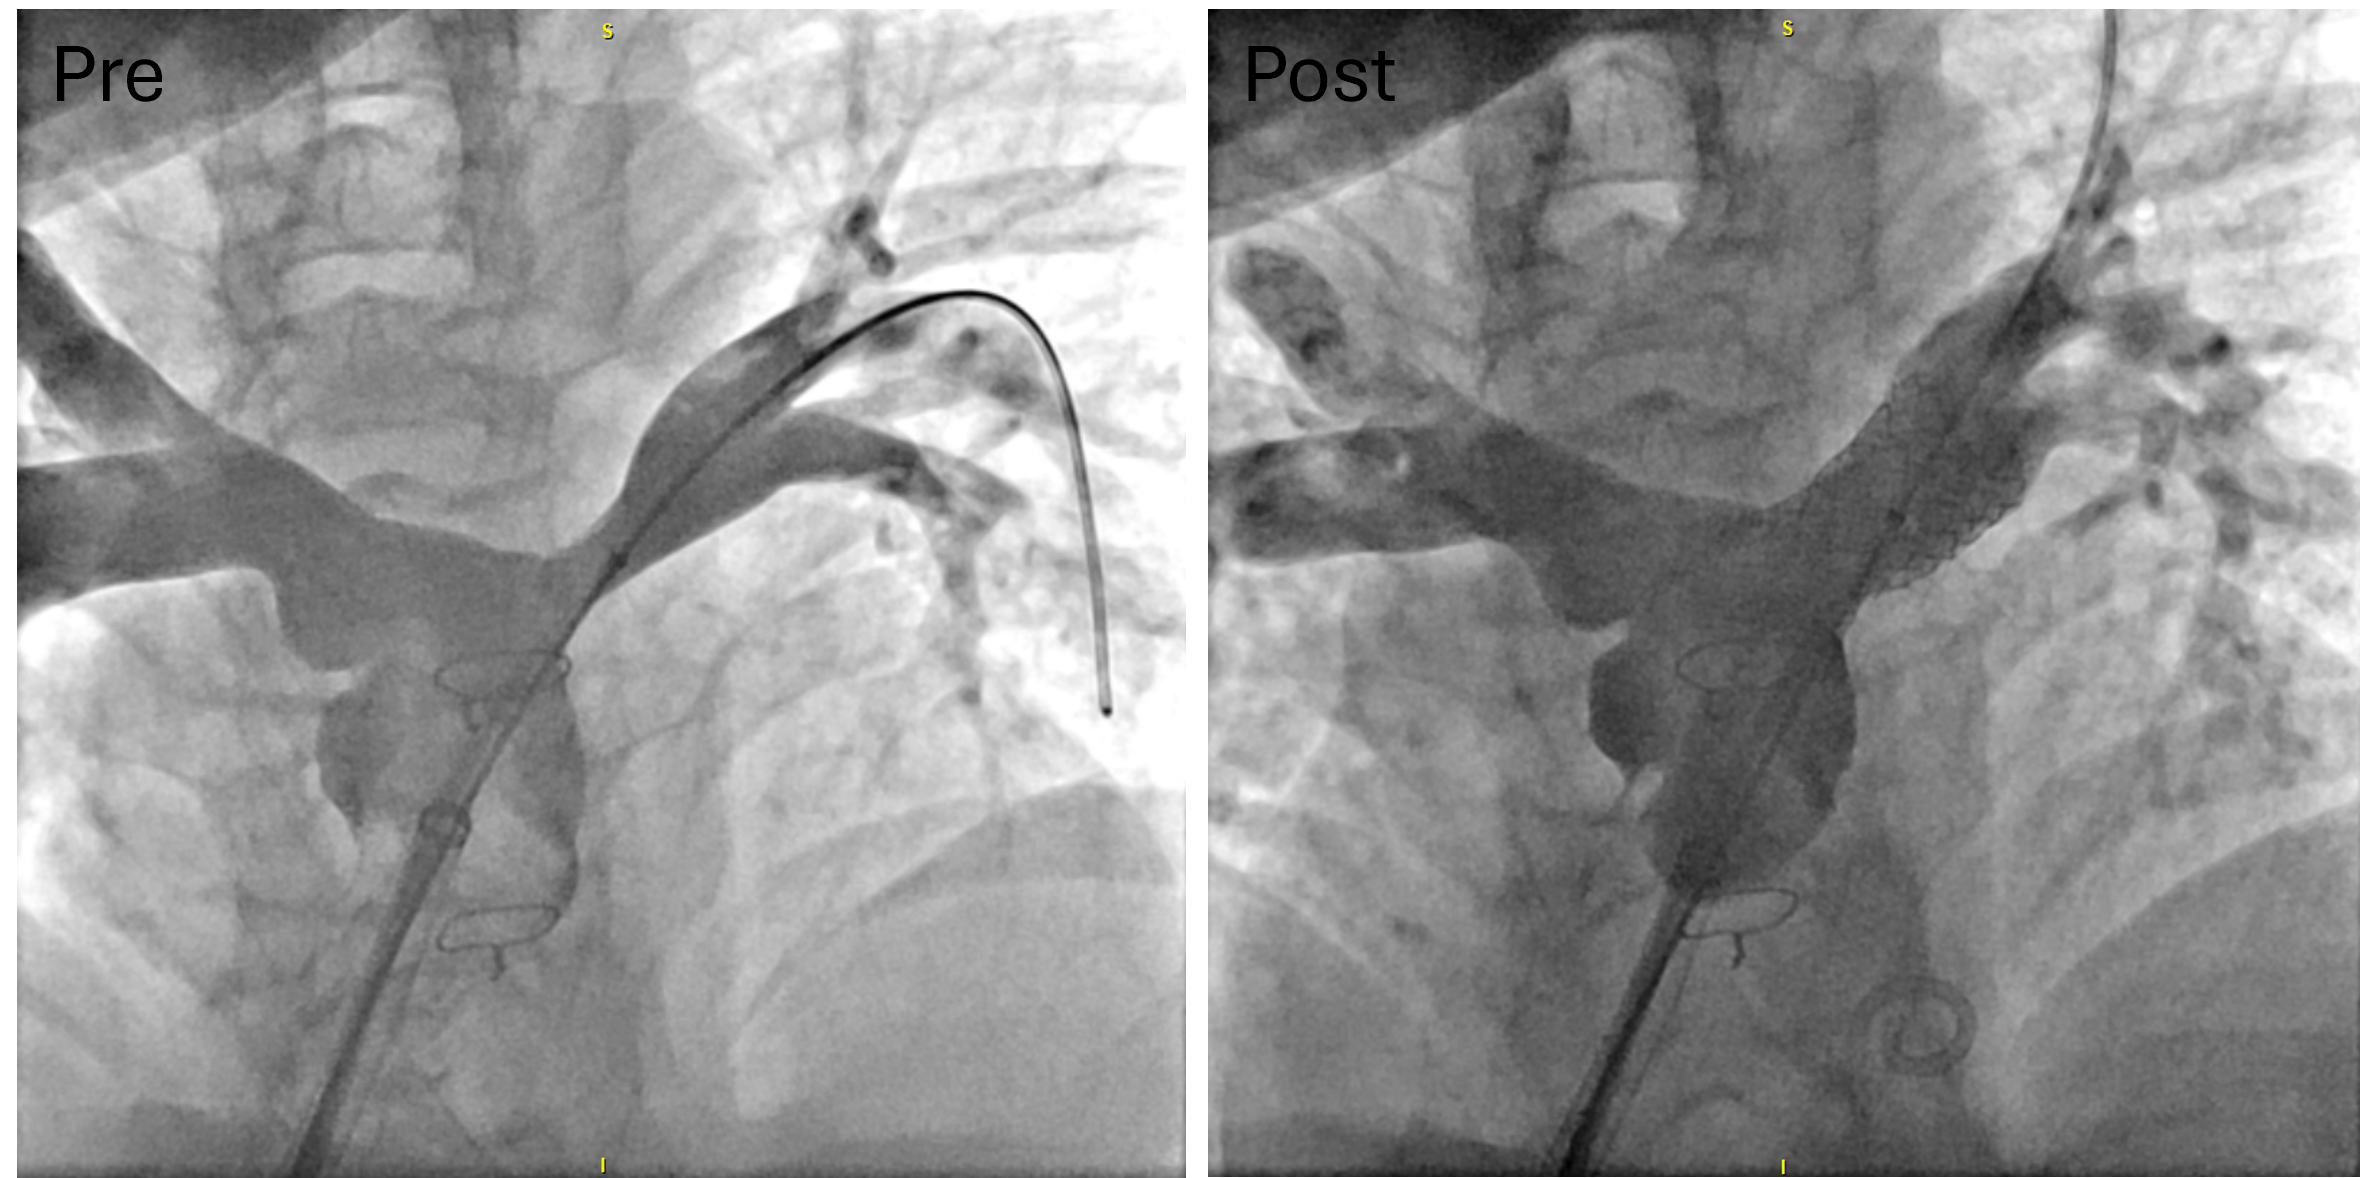

From a procedural standpoint, general anesthesia was utilized in 17 of the 23 procedures, while monitored anesthesia care was provided for the remaining 6 procedures. The patients typically underwent right heart hemodynamic catheterization, coupled with angiography for those with RVOTO, PAS, and SVS (Figures 1-3, pre). Additional retrograde left heart hemodynamic catheterization and angiography were performed for the patients with CoA (Figure 4, pre). The delivery sheath was as small as 7-French (Fr) in the femoral vein for the patients with RVOTO, PAS, and SVS, and 8-Fr in the femoral artery for patients with CoA, with ultrasound confirmation of a femoral arterial diameter greater than 3 mm prior to access in smaller patients. Stent size and pre-mount balloon diameter were chosen based on targeted pre-/post-stenotic vessel diameter, in addition to minimum waist diameter to allow secure delivery. Length was determined for adequate coverage of the targeted lesion. Rapid right ventricular pacing was performed only for CoA stent implantations. Selective post-implantation dilation with a non-compliant balloon was performed as needed to achieve the targeted diameter. Post-implant ultra-high-pressure dilation (≥ 20 atm) was performed on 8 stent grafts for full expansion (Table 2). Post-implantation angiography (Figure 1-4, post) and hemodynamic measurements were analyzed for all cases (Table 2).

The stent graft is pressure-mounted to the balloon, mitigating the risk of stent migration during advancement in addition to providing more low-profile delivery. We typically employed a long sheath for stent graft delivery but noted that passage between vessels did not require the advancement of a sheath prior to stenting, which dramatically reduced the risk of extravascular bleeding. Sheathless delivery enabled the creation of extravascular shunts, including the Reverse Potts Shunt, for patients with severe pulmonary hypertension,7 as well as a venous reconstruction of a chronic superior vena cava (SVC) occlusion that allows primary passage of the stent graft without sheath dilation of the tract.8